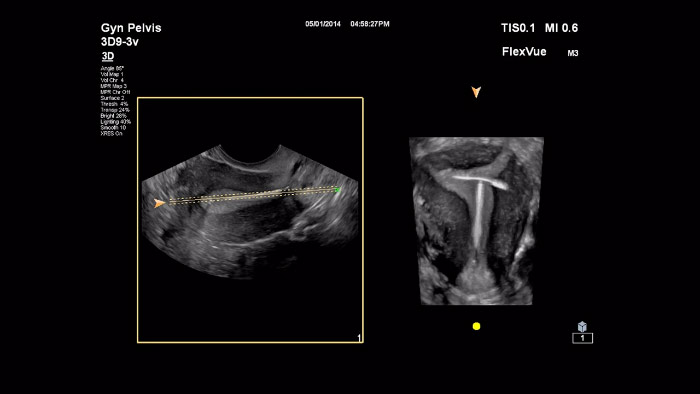

Demonstração do FlexVue e do FlexVue Volume da Philips pelo Dr. Michael Ruma

Neste vídeo, o Dr. Michael Ruma apresenta o FlexVue e o RexVue Volume, ferramentas avançadas de avaliação 3D da Philips. O FlexVue e o Flexvue Volume permitem uma visualização fácil de vistas anatómicas tecnicamente difíceis a partir de volumes 3D que são essenciais para o diagnóstico de patologias obstétricas/ginecológicas

Demonstração do FlexVue e da Vista ortogonal da Philips pelo Dr. Michael Ruma

Neste vídeo, o Dr. Michael Ruma apresenta o FlexVue e a Vista ortogonal, ferramentas avançadas de avaliação 3D da Philips em casos clínicos para obstetrícia e ginecologia.